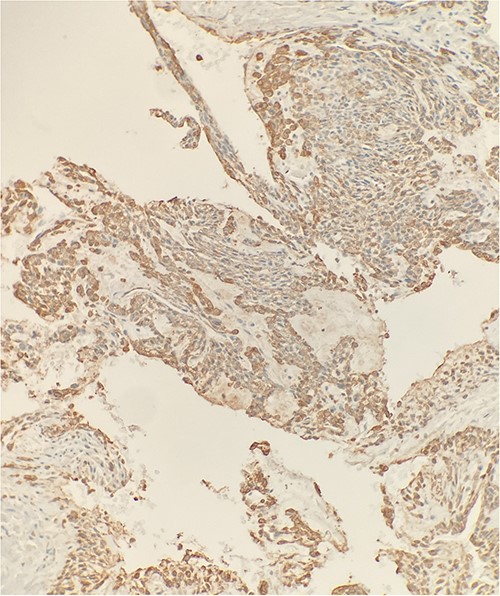

The excised mass was a fragment of tan red soft tissue measuring 0.7 × 0.4 × 0.4 cm. Microscopic examination reveals that tumor is composed of epithelioid bland cells forming gland-like architecture with scant mucinous material (Fig. 1). Without immunohistochemical stain, the morphological features are diagnostic for adenocarcinoma. However, in order to rule out other diagnostic possibility, we performed smooth muscle actin (SMA) immunohistochemical stain. The tumor cells turn out to be positive for SMA (Fig. 2). Combined with this immunoprofile, the final diagnosis of glomus tumor was rendered. The diagnosis of glomus tumor was confirmed with second opinion at world renowned institute.

Immunohistochemical stain reveals that tumor cells are positive for SMA. IHC ×20.

Careful evaluation of the pathological findings is essential to distinguish between glomus tumors and adenocarcinoma. SMA is a specific marker with 99% specificity for the diagnosis of glomus tumor [2]. SMA is commonly used to identify myoepithelial cells, smooth muscle cells and myofibroblasts in normal, reactive or neoplastic tissue, which should not be seen in adenocarcinoma [9]. In our report, the initial evaluation on morphology suggested adenocarcinoma because of glandular like structures. Because of the positive of SMA, the final diagnosis of glomus tumor was made. Further studies including immunohistochemical stain are necessary to fully understand the histological similarities and dissimilarities between the two types of tumors, in order to differentiate the benign lesions from malignant neoplasms.